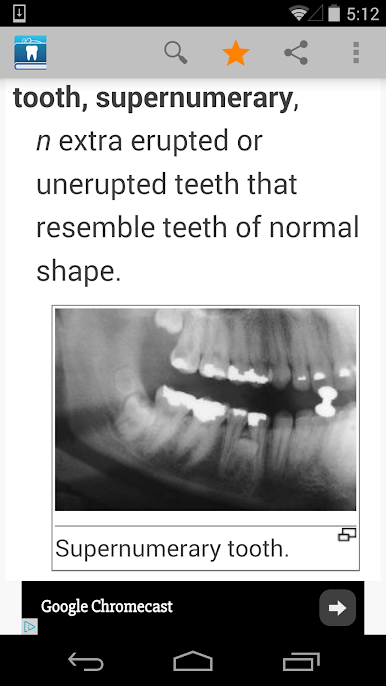

* Clear, in-depth definitions of dental terminology, including entries on diseases, causes, treatment methods, oral hygiene, and dental tools, as well as illustrations, photographs, and X-ray images.